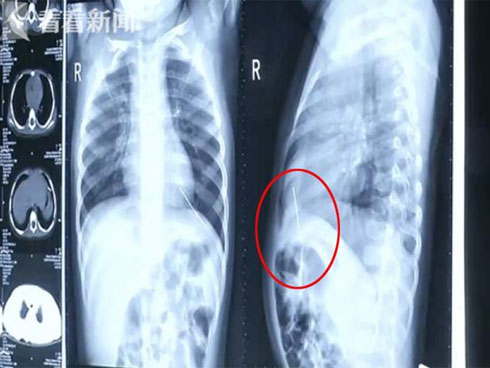

Sau khi kiểm tra và chụp X- quang, bác sĩ nói rằng đã tìm thấy một dị vật lạ ở khoang ngực của bé gái Chenchen. Khi soi kỹ hơn, hóa ra đó là một cây kim dài 4,5 cm đang nằm ở phần tâm thất trái của cô bé. Đây chính là nguyên nhân khiến cô bé bị ho suốt thời gian qua. Nghe tin này, bố mẹ của Chenchen đã vô cùng hoảng sợ và choáng váng. Họ không thể hiểu tại sao cây kim lại nằm trong cơ thể con gái.

Cây kim dài 4,5 cm đâm vào tâm thất trái của cô bé.